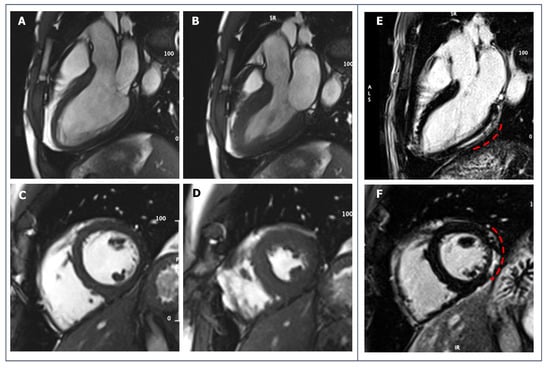

5.1. Hypertrophic Cardiomyopathy

5.2. Dilated Cardiomyopathy

5.3. Arrhythmogenic Cardiomyopathy

5.4. Non-Ischemic Scar

5.5. Left Ventricular Non-Compaction

5.6. Anomalies of the Coronary Artery Origin